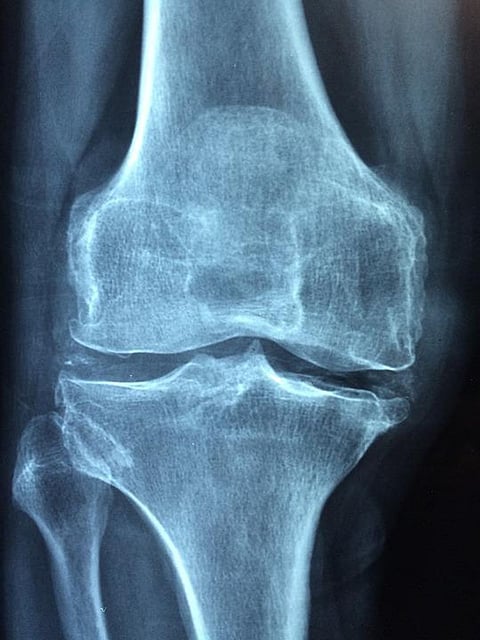

The team's approach focused on the knee joint, one of the most complex mechanical systems within the human body and a critical player during gait. The knee joint's motion is actuated by several skeletal muscles along its articular surfaces, and its center of rotation moves. "Our new design features a parallel knee joint to improve the bio-imitability and adaptability of the exoskeleton," explained Weihai Chen, professor at Beihang University. Movement transparency is critical when wearing a robot for gait rehab.